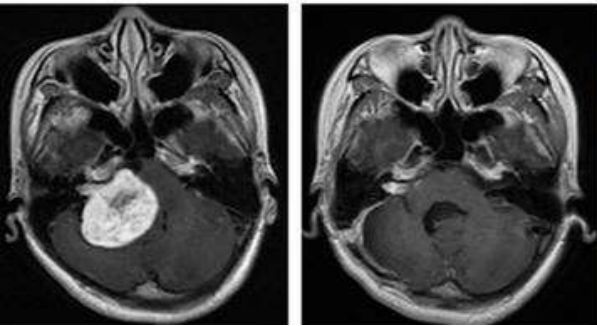

质子的辐射可以最大限度降低对正常组织的伤害,对目标肿瘤细胞造成最大的损害。以儿童髓母细胞瘤为例,我们可以看到普通放疗产生的大部分副作用,质子都完美的规避了。

普通放疗全部颅脑都受到照射

质子治疗